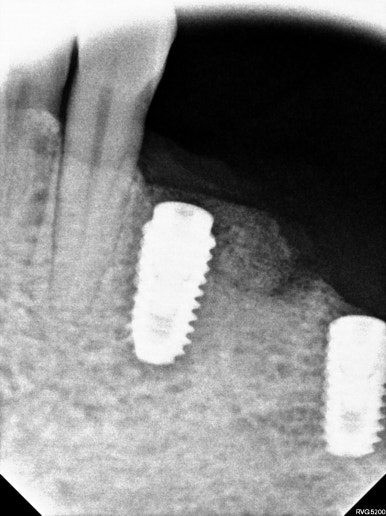

#34,36,37 자리에 임플란트를 식립할 예정이었어요.

#34번 부위는 임플란트를 위치시키고 나면 협측으로 뼈이식을 반드시 넉넉하게 해야할 모양새였습니다.

비교적 뽑은지 오래되었던 #36,37 치아는 잇몸뼈가 넉넉하게 보였습니다.

두 큰어금니 부위는 하치조신경관(아래이틀신경)만 조심해서 적절한 임플란트를 심어놓으면 되었습니다.